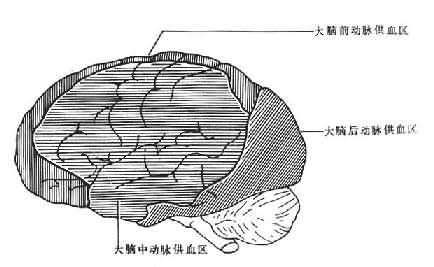

此外,损伤的部位还和局部的血管分布和血管的状态有关。在发生缺血(氧)时,动脉血管的远心端供血区域最易发生灌流不足。大脑分别由来自颈内动脉的大脑前动脉、大脑中动脉和来自椎动脉的大脑后动脉供血。其中大脑前动脉供应大脑半球的内侧面和大脑凸面的额叶、顶叶近矢状缝宽约1~1.5cm的区域。大脑中动脉则供应基底核、纹状体、大脑凸面的大部区域。而大脑后动脉则供应颞叶的底部和枕叶。这样在3支血管的供应区之间存在一个C形分布的血供边缘带,该带位于大脑凸面,与矢状缝相平行,且旁开矢状缝1~1.5cm(图16-19)。一旦发生缺血性脑病,该区域则最易受累。然而并非每例缺血性脑病病灶都呈C型,病灶的形状还受局部血管管径的影响,如果某支血管管径相对较小,或局部动脉粥样硬化,则其供血区较易受累。

图16-19大脑前、中、后动脉供血区之间的C形边缘带示意图